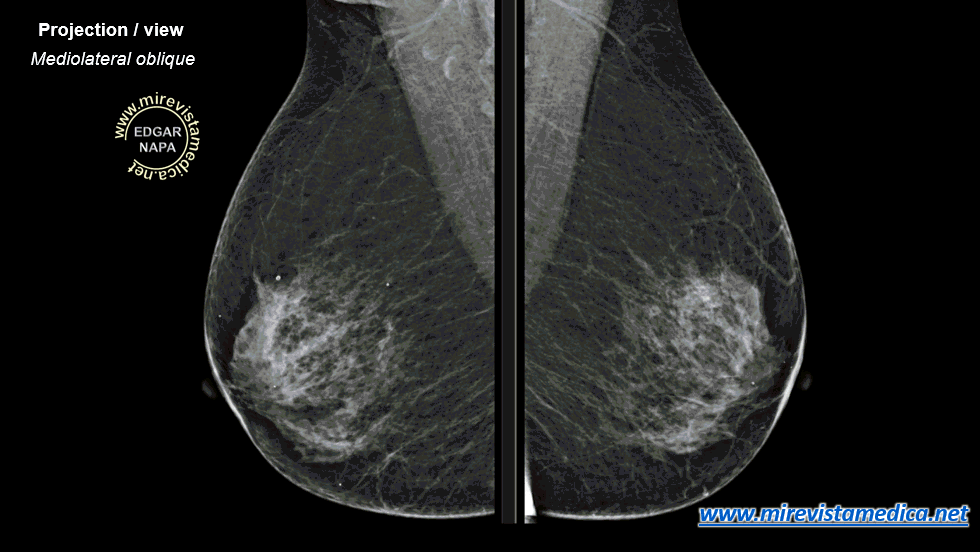

MAMOGRAFÍA (Mx)